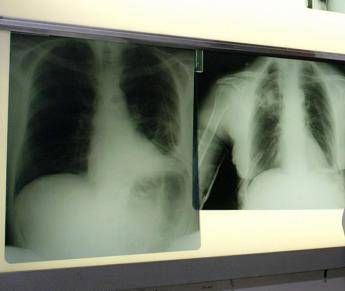

Portare innovazione terapeutica per i pazienti con carcinoma polmonare a piccole cellule (Sclc), una delle forme più complesse di tumore al polmone. E' l'impegno che PharmaMar rinnova in occasione della Giornata mondiale del tumore al polmone, che si celebra oggi, 1 agosto, con il suo approccio "unico e innovativo" ispirato dal mare per la scoperta di nuove terapie oncologiche.

Il tumore al polmone – ricorda l'azienda in una nota – continua a essere una delle neoplasie più diffuse e letali in Italia e nel mondo. Ogni anno, solo in Italia, vengono diagnosticati 44.831 nuovi casi. Circa il 12% riguarda il carcinoma polmonare a piccole cellule, una forma aggressiva e a rapida progressione, per la quale le opzioni terapeutiche sono rimaste a lungo limitate. Negli ultimi anni, tuttavia, i progressi nel trattamento dello Sclc hanno aperto nuove prospettive. Tra questi, un composto sintetico di origine marina – estratto dall'invertebrato Ecteinascidia turbinata – che ha dimostrato risultati promettenti in combinazione come terapia di mantenimento in prima linea per i pazienti con Sclc in stadio esteso (Es-Sclc), una delle forme tumorali più aggressive e con maggiori bisogni clinici insoddisfatti. Come dimostrano i risultati dello studio di fase 3 IMforte, presentato lo scorso giugno all'Asco Annual Meeting 2025 di Chicago, il Congresso dell'American Society of Clinical Oncology, il composto sintetico di origine marina, in combinazione con immunoterapia, riduce del 46% il rischio di progressione della malattia o di morte, con una sopravvivenza mediana globale di 13,2 mesi rispetto ai 10,6 mesi con la sola immunoterapia. "Il carcinoma polmonare a piccole cellule è una delle forme più aggressive e difficili da trattare di tumore del polmone – spiega Silvia Novello, direttrice della Struttura complessa a direzione universitaria di Oncologia medica dell'Ospedale San Luigi di Orbassano e professoressa ordinaria di Oncologia medica all'Università degli Studi di Torino – Nella maggior parte dei casi, la diagnosi avviene quando la malattia è già in fase avanzata e le opzioni terapeutiche a disposizione sono limitate. I risultati dello studio IMforte rappresentano un'importante novità: la nuova combinazione ha dimostrato un beneficio clinico significativo, con un miglioramento della sopravvivenza globale e della sopravvivenza libera da progressione. Si tratta di dati estremamente incoraggianti – sottolinea – che potrebbero cambiare concretamente l'approccio terapeutico per questi pazienti e aprire una nuova prospettiva di trattamento per una popolazione finora e per troppo tempo priva di alternative efficaci".